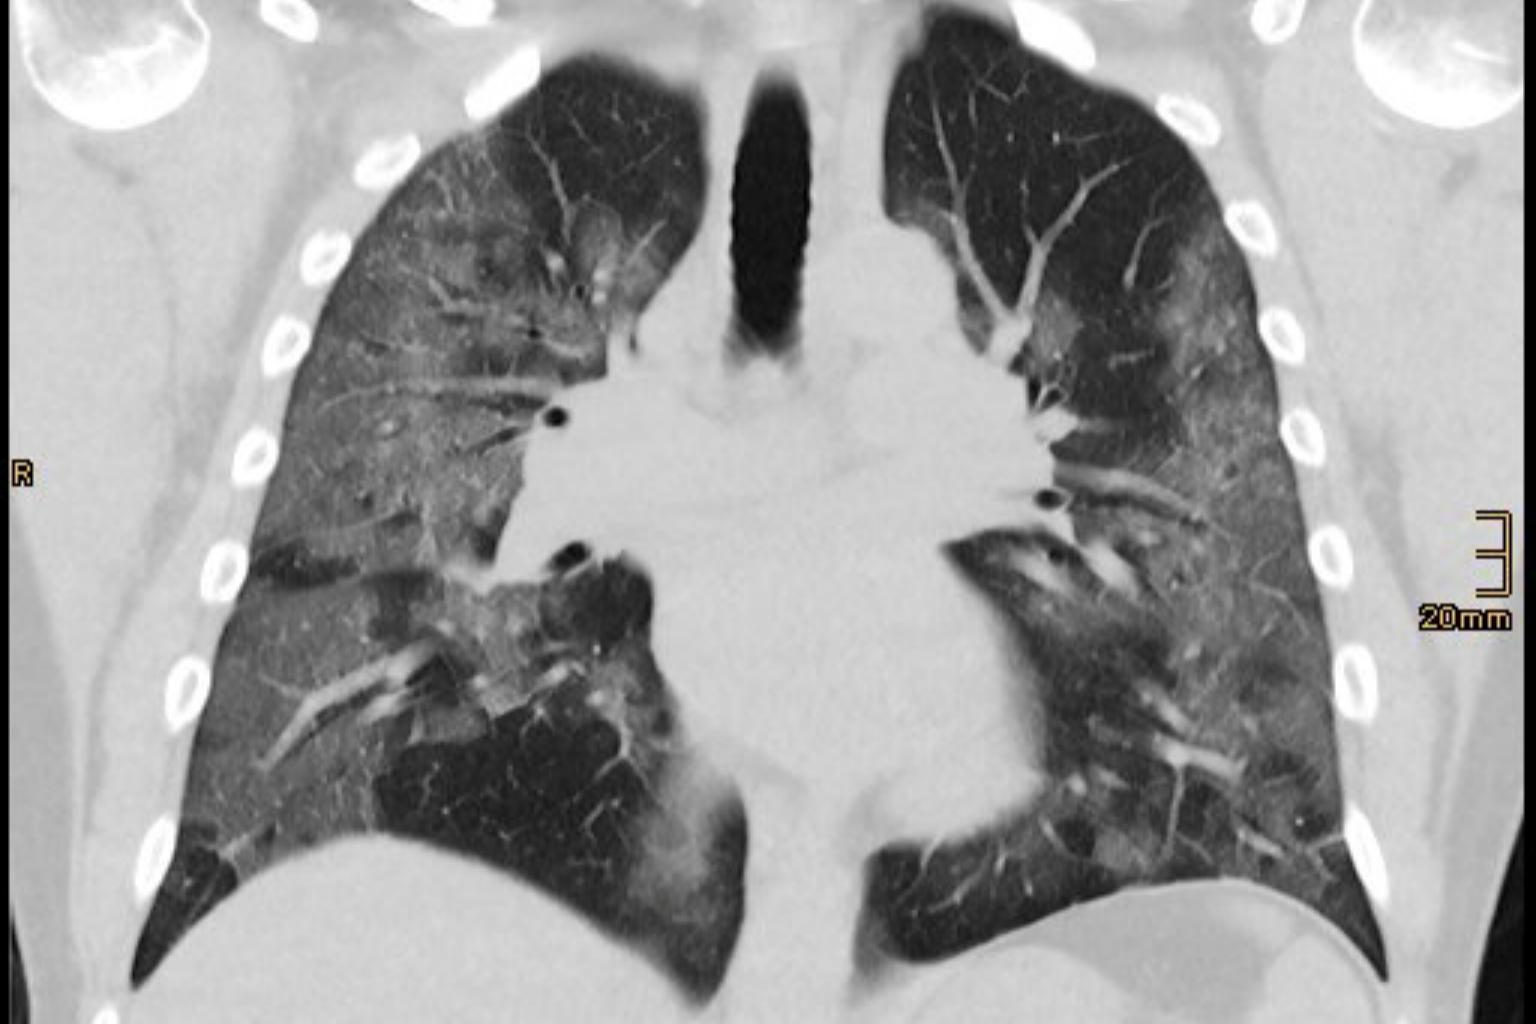

A CT scan showing the lungs of coronavirus patient Andre Bergmann.

<p>A CT scan picture shows lungs of 48-year-old coronavirus disease (COVID-19) patient Andre Bergmann, in this screen grab released on April 14, 2020 by the Bethanien Hospital lung clinic in Moers, Germany. HOSPITAL BETHANIEN MOERS/THOMAS VOSHAAR/Handout via REUTERS. ATTENTION EDITORS - THIS IMAGE HAS BEEN SUPPLIED BY A THIRD PARTY. MANDATORY CREDIT.</p>

"I realised as soon as I saw the first CT scan ... that this had nothing to do with what we had seen and done for the past 40 years," he told Reuters.

He and other doctors think other tests can help before intubation. Dr Voshaar looks at a combination of measures, including how fast the patient is breathing and their heart rate. His team are also guided by lung scans.